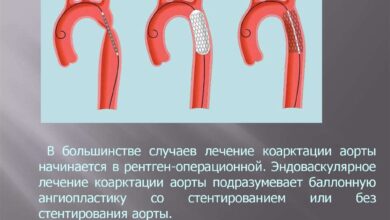

Лечение и профилактика

Лечение эндокардита зависит от его формы и тяжести. В некоторых случаях может потребоваться хирургическое вмешательство для замены пораженных клапанов.